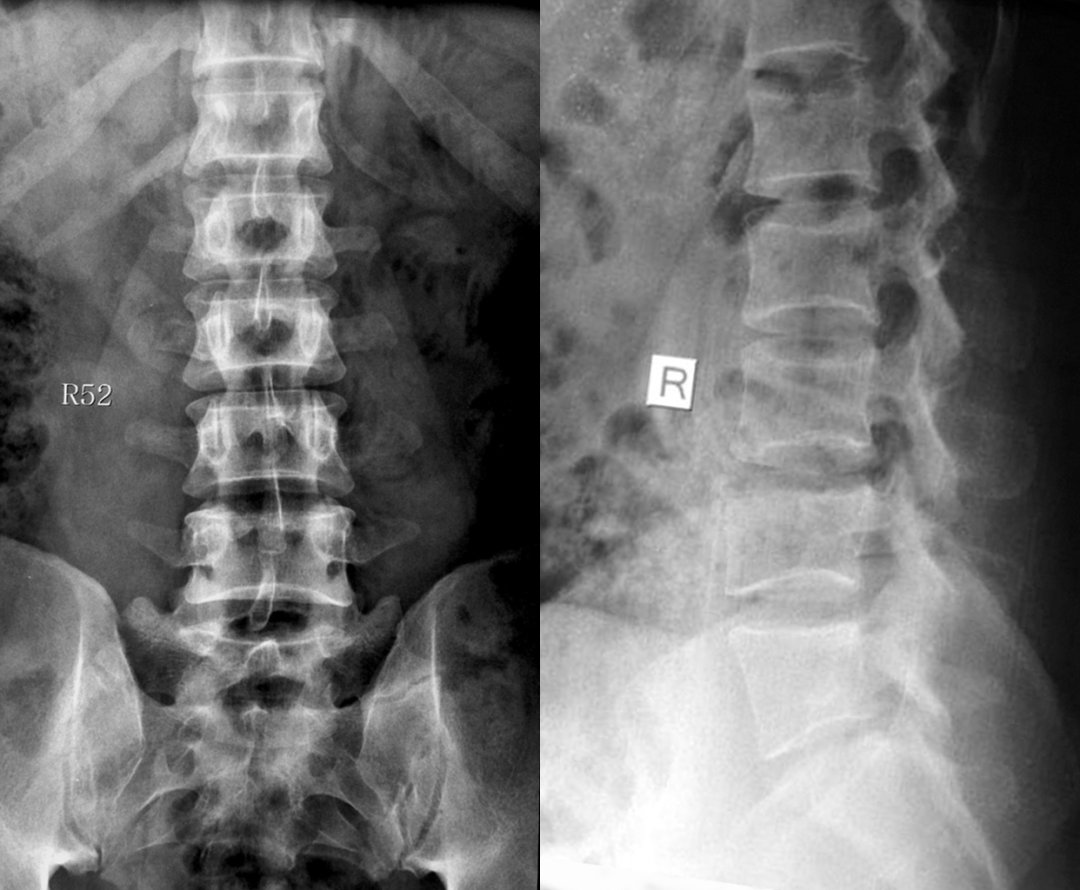

如何在临床阅片准确判断是一个很重要的问题,这里介绍一个最准确的判断方法。

这是一个最关键和准确的鉴定方法,国内著名骨放射学家杨世埙教授指导过,只要大家留意关注腰椎横突"三长/四翘/五宽",L3横突是最长的,L4横突是上翘的,L5横突最宽,特别用在胸椎腰化合并L5骶化的时候比较实用。

目前,腰骶移行椎以 Castellvi 的分类方法最为常用。其主要根据横突形态及其与骶骨、髂骨是否融合或形成假关节而分为 4 型,Ⅰ、Ⅱ、Ⅲ型又根据单、双侧分为A、B两个亚型。

它与腰骶部疼痛存在密切的相关性是不可忽视的, 并干扰诊断与之症状相近的其它疾病, 如椎间盘突出、致密性骨炎、强直性脊柱炎等等, 当然这其中有些疾病可以并存, X 线、CT 检查在腰骶部移行椎的诊断中有重要意义, 不仅能对本病做出诊断, 并且有助于鉴别诊断。